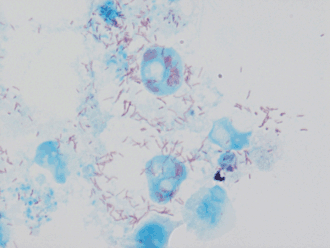

Возбудителем инфекции является бактерия Rickettsia conorii, которая паразитирует внутриклеточно и внутриядерно. Как правило, она обладает размерами 0,3—0,8 мкм и с точки зрения патогенеза представляет опасность для кроликов, морских свинок, сусликов, обезьян, белых мышей и белых крыс. У самцов этих животных она может быть выявлена в клетках мезотелия и служить причиной периорхита. У заболевших людей присутствие возбудителя возможно обнаружить в крови во время первых суток лихорадочного периода, в розеолах кожи и в первичном аффекте, который неизбежно возникает в месте укуса клеща[3]. Морфологические, тинкториальные и иммунологические свойства бактерии Rickettsia conorii имеют много сходного с Rickettsia rickettsii, которая является возбудителем другой опасной болезни — пятнистой лихорадки Скалистых гор[6].